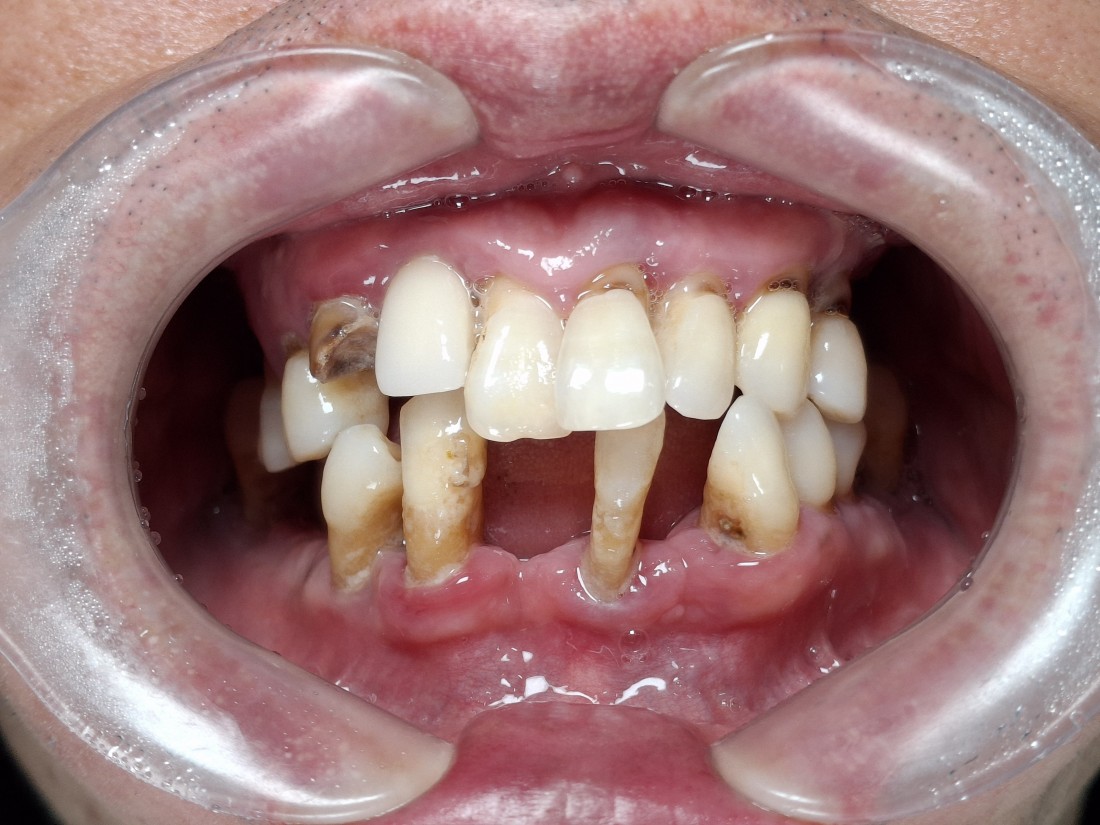

광주 전체임플란트

치료 케이스가 많은 치과가

잘하는 치과입니다.

광주 전체임플란트 케이스만

수 백가지로 정리하여

위의 홈페이지에 올려드리고 있는데요.

치과의사도 경험이 풍부한 사람이

여러 케이스를 다 다뤄보았기 때문에

좋은 임플란트 실력을 믿을 수 있습니다.

무엇보다도 전체임플란트 중에서

특히 앞니임플란트가

자연스럽고 예쁘게 완성이 되는지

많이 걱정하실텐데요.